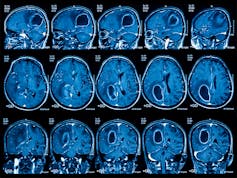

Currently, scientists use a variety of clever techniques to understand the structure and function of the brain, such as magnetic fields, X-rays and radioactive chemicals. As ingenious as these methods are, they are unable to provide a full measure of the tremendous complexity of how the brain operates.

Studies using brain imaging machines have examined whether parts of the brains of individuals with autism may be different in size, shape or function.

However, the only consistent finding is just how much inconsistency there is. Not every individual with autism has differences in the size or pattern of growth of different brain regions. For those individuals who do, it is unclear how this may relate to their autistic behaviours.

A great deal of brain imaging research has examined the connections within the brain of individuals with autism. Connectivity is a measure of how well and how much two brain areas communicate with each other. In the study of autism, scientists distinguish between short-range connections (between neighbouring brain areas) and long-range connections (between brain areas further apart).

One prominent theory that has emerged from brain imaging studies is that some individuals with autism may have under-connectivity in long-range connections, but over-connectivity in short-range connections.

If found to be accurate, these brain differences may be able to explain why some individuals with autism have difficulties with complex tasks that require the integration of information from multiple brain regions (such as cognitive and social abilities), but have no difficulties, or even enhanced abilities, for tasks that require less integration across brain areas (such as sensory processing).